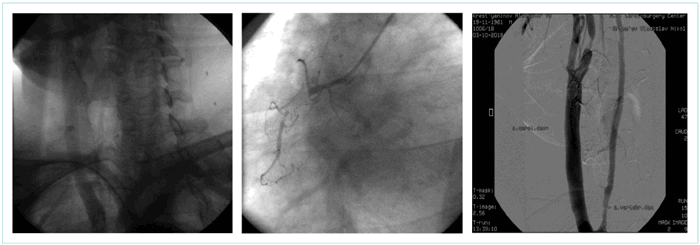

- Попытки катетеризации общих сонных артерий правым дистальным доступом были безуспешными, и мы воспользовались левым дистальным лучевым доступом с использованием катетера Sim (рис. 1).

Рисунок 1. Контрольная аортография, выявление а. lusoria и хронической окклюзии правой коронарной артерии в проксимальном сегменте

Figure 1. Control aortography, detection of a. lusoria and a chronic occlusion of the right coronary artery in the proximal segment

Таким образом, перед нами был пациент с аномальной дугой аорты (почти горизонтально расположенной, с укороченным восходящим отделом) и ее аномальными ветвями (a. l., с низким отхождением правой общей сонной артерии, отхождением правой позвоночной артерии от проксимальной порции правой общей сонной артерии), с атеросклеротическим поражением: хронической окклюзией правой коронарной артерии в проксимальном сегменте при правом типе коронарного кровоснабжения миокарда, со значимым стенозом правой внутренней сонной артерии (рис. 2).